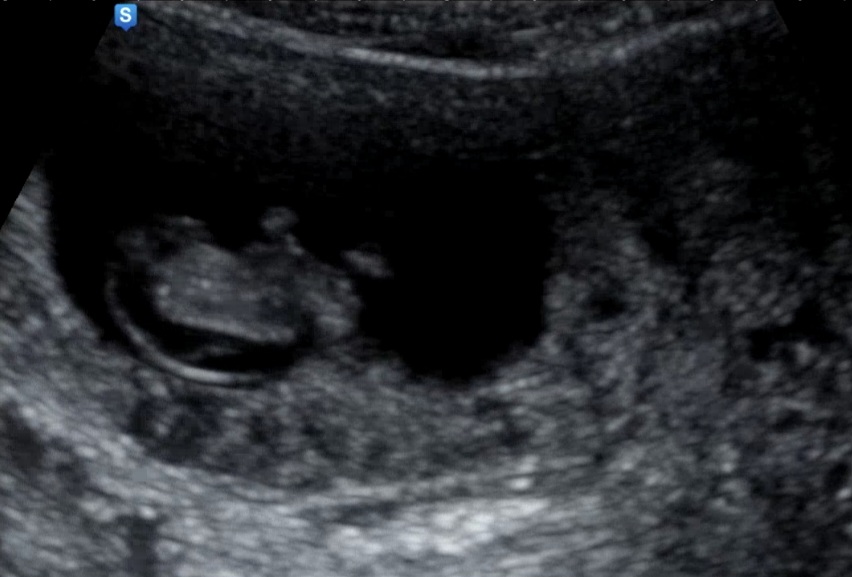

10주차 초음파 목덜미

10주 막 됐을 때 초음파 찍어주시던 의사쌤이 목덜미가 두껍다면서 신경관결손 우려얘길하셔서 걱정돼요ㅜ 크기는 3.4cm정도에요..